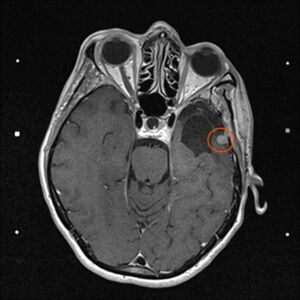

Am 03. November war mein Kontrollbesuch beim MRT. Leider ist ein kleiner Befund aufgetaucht. Schau das Video, dann kannst Du sehen.

Nun kann sich zeigen, ob die menschliche Medizin eine Lösung für mich hat. Möglichkeiten gibt es. Sogar mindestens eine, die der Neurochirurg als fein und elegant beschreibt. Gamma-Knife, eine Strahlentherapie. Klingt etwas nach Star Wars – man wird sehen, etwas abwarten ist auch drin.

Am 29.4.2021 war ich zum Kontroll-MRT drei Monate nach der hochmodernen Strahlentherapie, dem Gamma-Knife. Leider ist das Ergebnis: den Tumor hat diese Behandlung nicht beeindruckt, keine Änderungen zu erkennen. Der Arzt schlägt eine weitere Kontrolle in 6 Monaten vor. Ich finde es etwas schwer, dieses Ergebnis einzuordnen. Aber so ist es nunmal. Vielleicht ist es ja normal, und wird erst später gut (siehe Punkt 4).

Heute war ich im MRT im Bremen. Der Befund des auswertenden Arztes ist, dass er der Meinung ist, dass der Tumor etwas gewachsen ist. Ich habe mir die Bilder angesehen und versucht diese Aussage zu verstehen. Vermutlich ist sie richtig, aber das Wachstum ist nicht heftig nur vielleicht von 0,7 cm auf 0,8 cm. Aber Gamma-Knife hat es offensichtlich nicht entfernt.